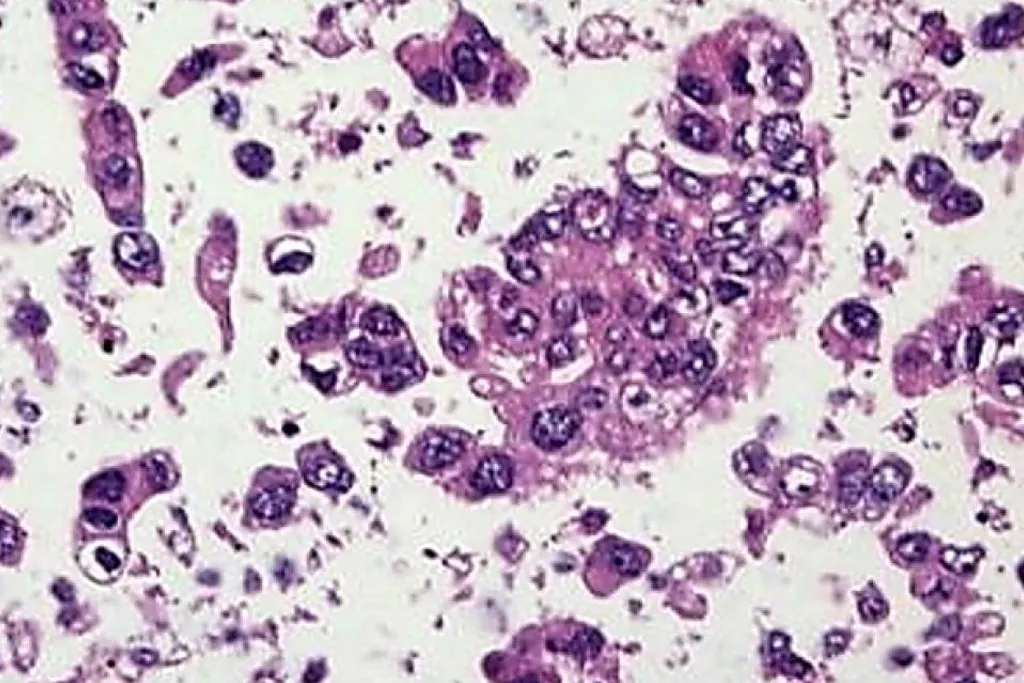

Image Gallery2

2. Image Courtesy of Cytology Dept. Groningen University Hospital, Netherlands